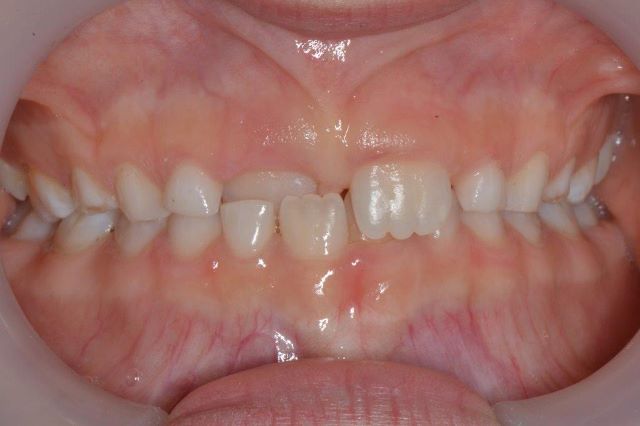

צפיפות שיניים

צפיפות מוגדרת כאשר ישנה חפיפה בין שיניים (האחת על גבי השנייה) ולרוב, רוחב קשת השיניים קטן מרוחב השיניים